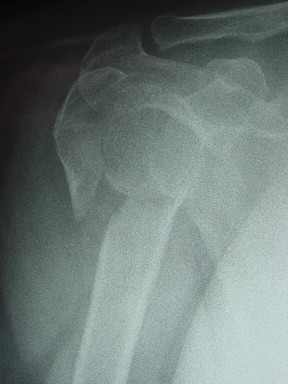

Re: Перелом шейки плеча

сделать закрытую репозицию с помощью ЭОПа совсем не сложно, после этого еще проще провести 3-6 спиц и получить красивую рентгенограмму. Есть только небольшая проблема это ROTATOR CUFF. Для плечевого сустава только костное восстановление не достаточно. для функции плечевого сустава нужны вращатели.

Давайте представим себе состояние манжетки вращателей после вывиха плеча, а еще и с отрывным переломом бугров. Головка может и прирастет, еесли не будет аваскулярного некроза, но хорошего функционального результата не ждите.

Висеть будет красиво. У людей физически активного периода жизни нужно открыть, восстановить костную анатомию и восстановить сухожильный аппарат.

В этом плане Locking plate очень хороша так как позволяет начать движения сразу после операции.

Клинические снимки - 3 недели после операции